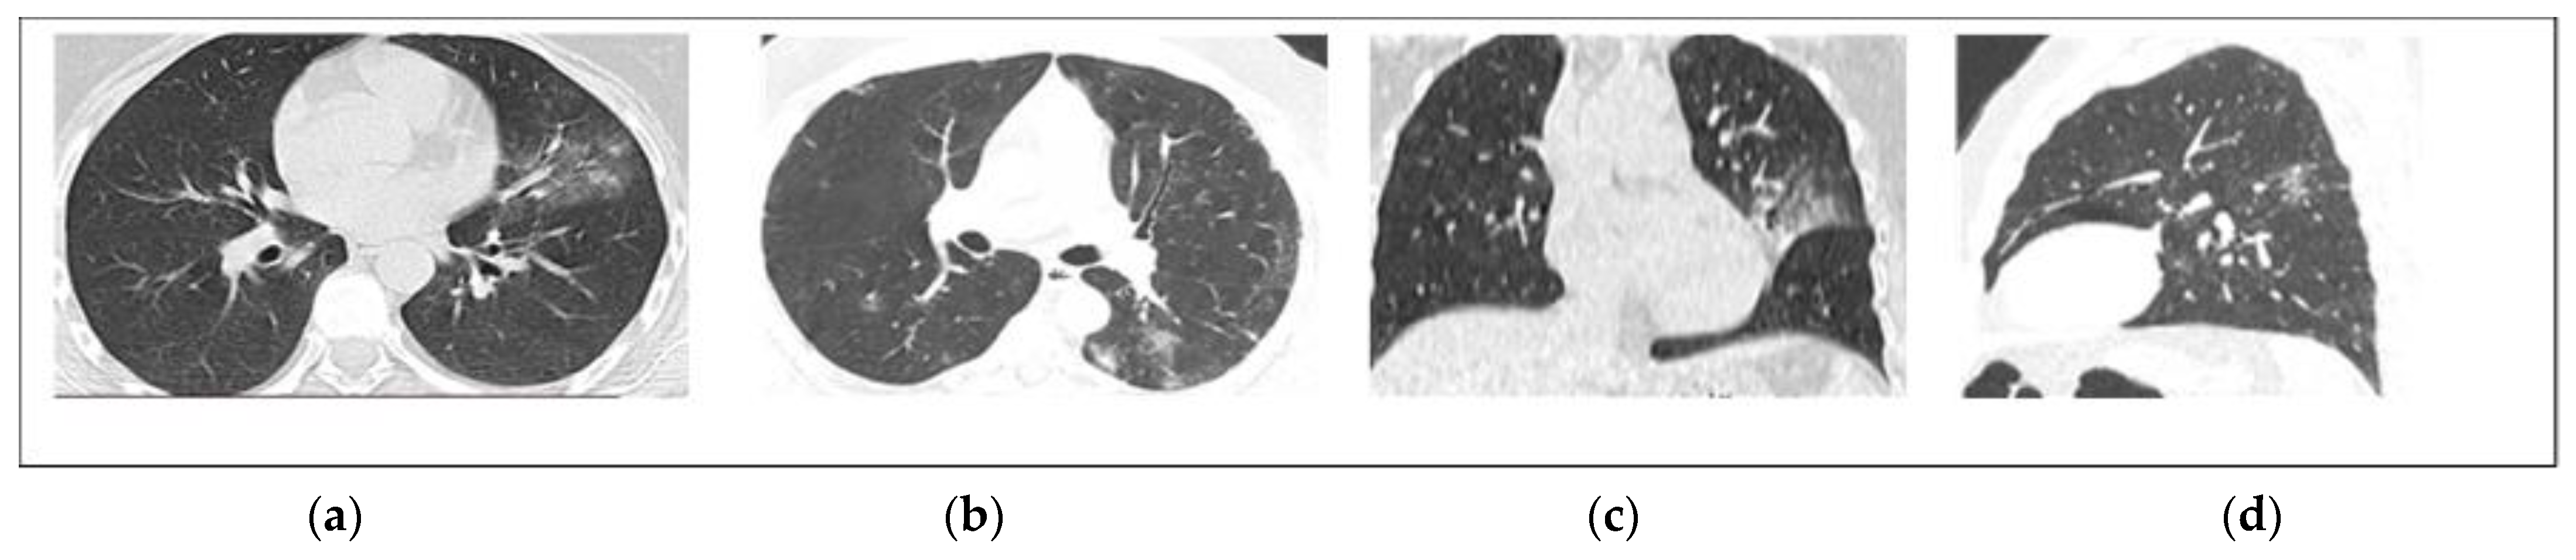

2.4. Qualitative CT Image Analysis

2.5. Quantitative CT Image Analysis